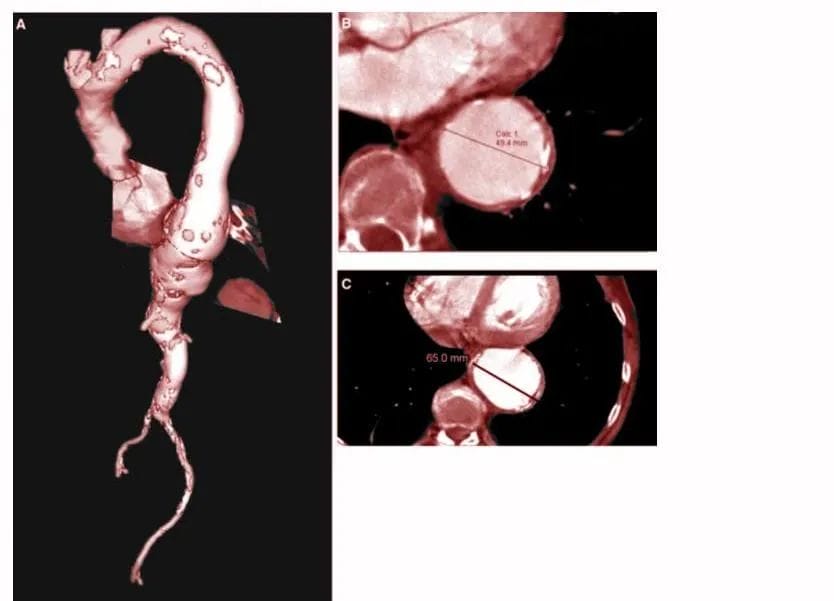

An aortic aneurysm refers to an abnormal bulge or dilation in the wall of the aorta — the main artery that carries blood from the heart to the rest of the body. It is generally classified into two main types: ascending aortic aneurysm and descending aortic aneurysm. The key difference between them lies in their location within the aorta and how they affect the heart and circulation. Understanding this distinction is crucial for accurate diagnosis and determining the most appropriate treatment approach.

In larger aneurysms, surgical intervention may be needed. Surgical repair of the aneurysm can be either open surgical repair which involves the replacement of the destructed section of the aorta with a piece of a graft material or stent aided endovascular repair (EVAR).